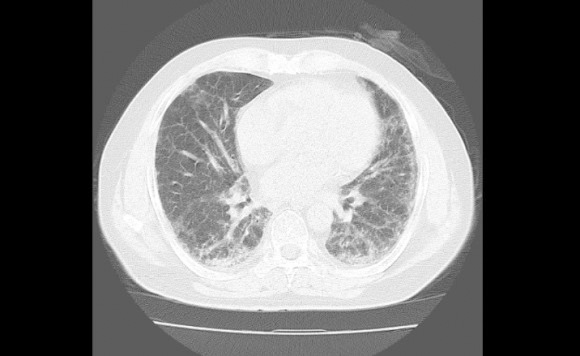

<간질성폐질환 CT 사진>

이 간질성폐질환은 종류가 150여개나 되는데 그 중에 가장 위험한 것은 특발성폐섬유화증입니다.